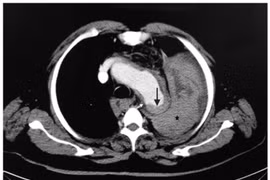

Tách thành động mạch chủ cấp là bệnh lý cực kỳ nguy hiểm, có tỷ lệ tử vong rất cao 1-2% mỗi giờ trong 24 giờ đầu nếu không được phát hiện sớm và xử trí kịp thời.

(khoahocdoisong.vn) - Phình động mạch chủ bụng thường liên quan đến những bệnh nhân có tiền sử hút thuốc lá, tăng huyết áp, tiểu đường... Bệnh không có triệu chứng nhưng vỡ sẽ gây tử vong nhanh chóng nên cần nhận biết và điều trị sớm.

Nếu sờ thấy bụng có khối u đập theo nhịp tim ở vùng giữa bụng trên rốn thì đây chính là dấu hiệu của chứng phình động mạch chủ, cho thấy sức khỏe của bạn đang nguy kịch.